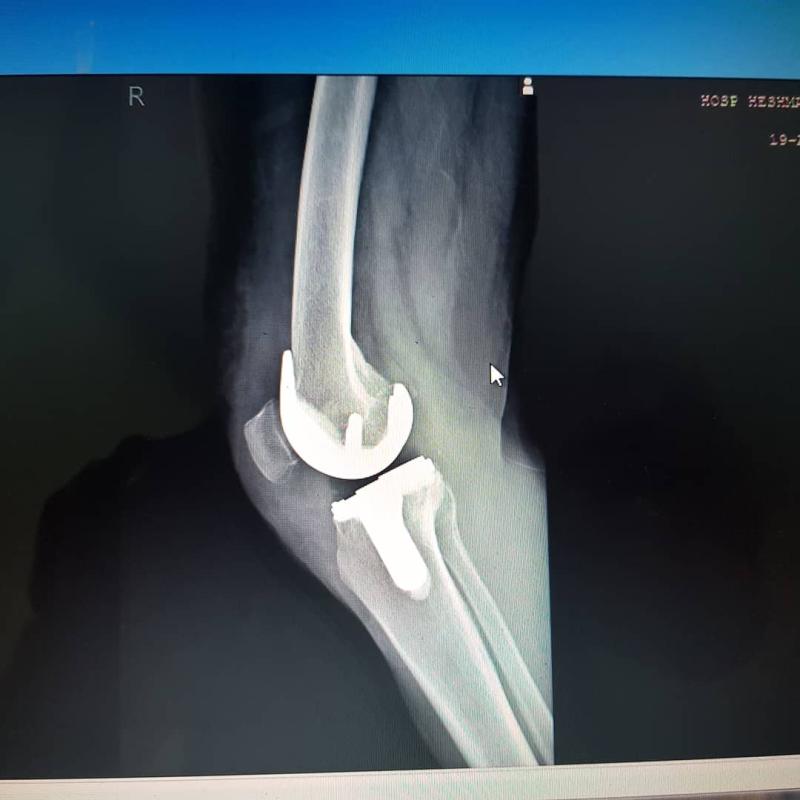

نمونه کارها